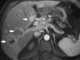

Calcified lymph nodes at porta hepatis